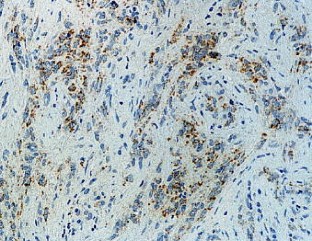

A chordoid glioma in the third ventricle was studied immunohistochemically and ultrastructurally. In this report, special attention is paid to the histogenesis in relation to the pathological appearance and unique anatomic location of this tumor. Light microscopic and immunohistochemical findings were similar to those reported previously. Ultrastructurally, microvilli were frequently seen, but three types of abnormal cilia were rarely observed. Basement membrane around the tumor cells and microvessels was extensive. Poorly to moderately developed intermediate (adherent) junctions were frequently seen. Resemblance of these ultrastructural features of the tumor to embryonic tanycytes suggests the tanycytic differentiation of chordoid glioma. Neuroradiologically, all of the previously reported cases of chordoid gliomas seem to arise in the anterior part of the third ventricular floor. This region includes the lamina terminalis, infundibular recess and median eminence, which corresponds to a tanycyte-rich area. These findings suggest a tanycytic origin of chordoid glioma.

Fig. 3.